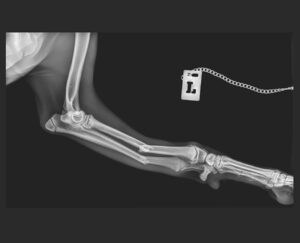

Mit dem Preisgeld möchten wir dieses Mal ganz konkret Simbad helfen. Simbad ist ein junger Galgorüde und wurde von einem Auto angefahren. Er musste notoperiert werden. Diagnose: beidseitiger Ellen- und Speichenbruch der Vorderläufe. Unsere spanischen Tierschutzkollegen, der Protectora in Villena, kümmern sich aufopferungsvoll um Simbad, obwohl das Geld schon an allen Ecken und Kanten fehlt. Übrigens: Simbad sucht noch ein liebevolles Zuhause.